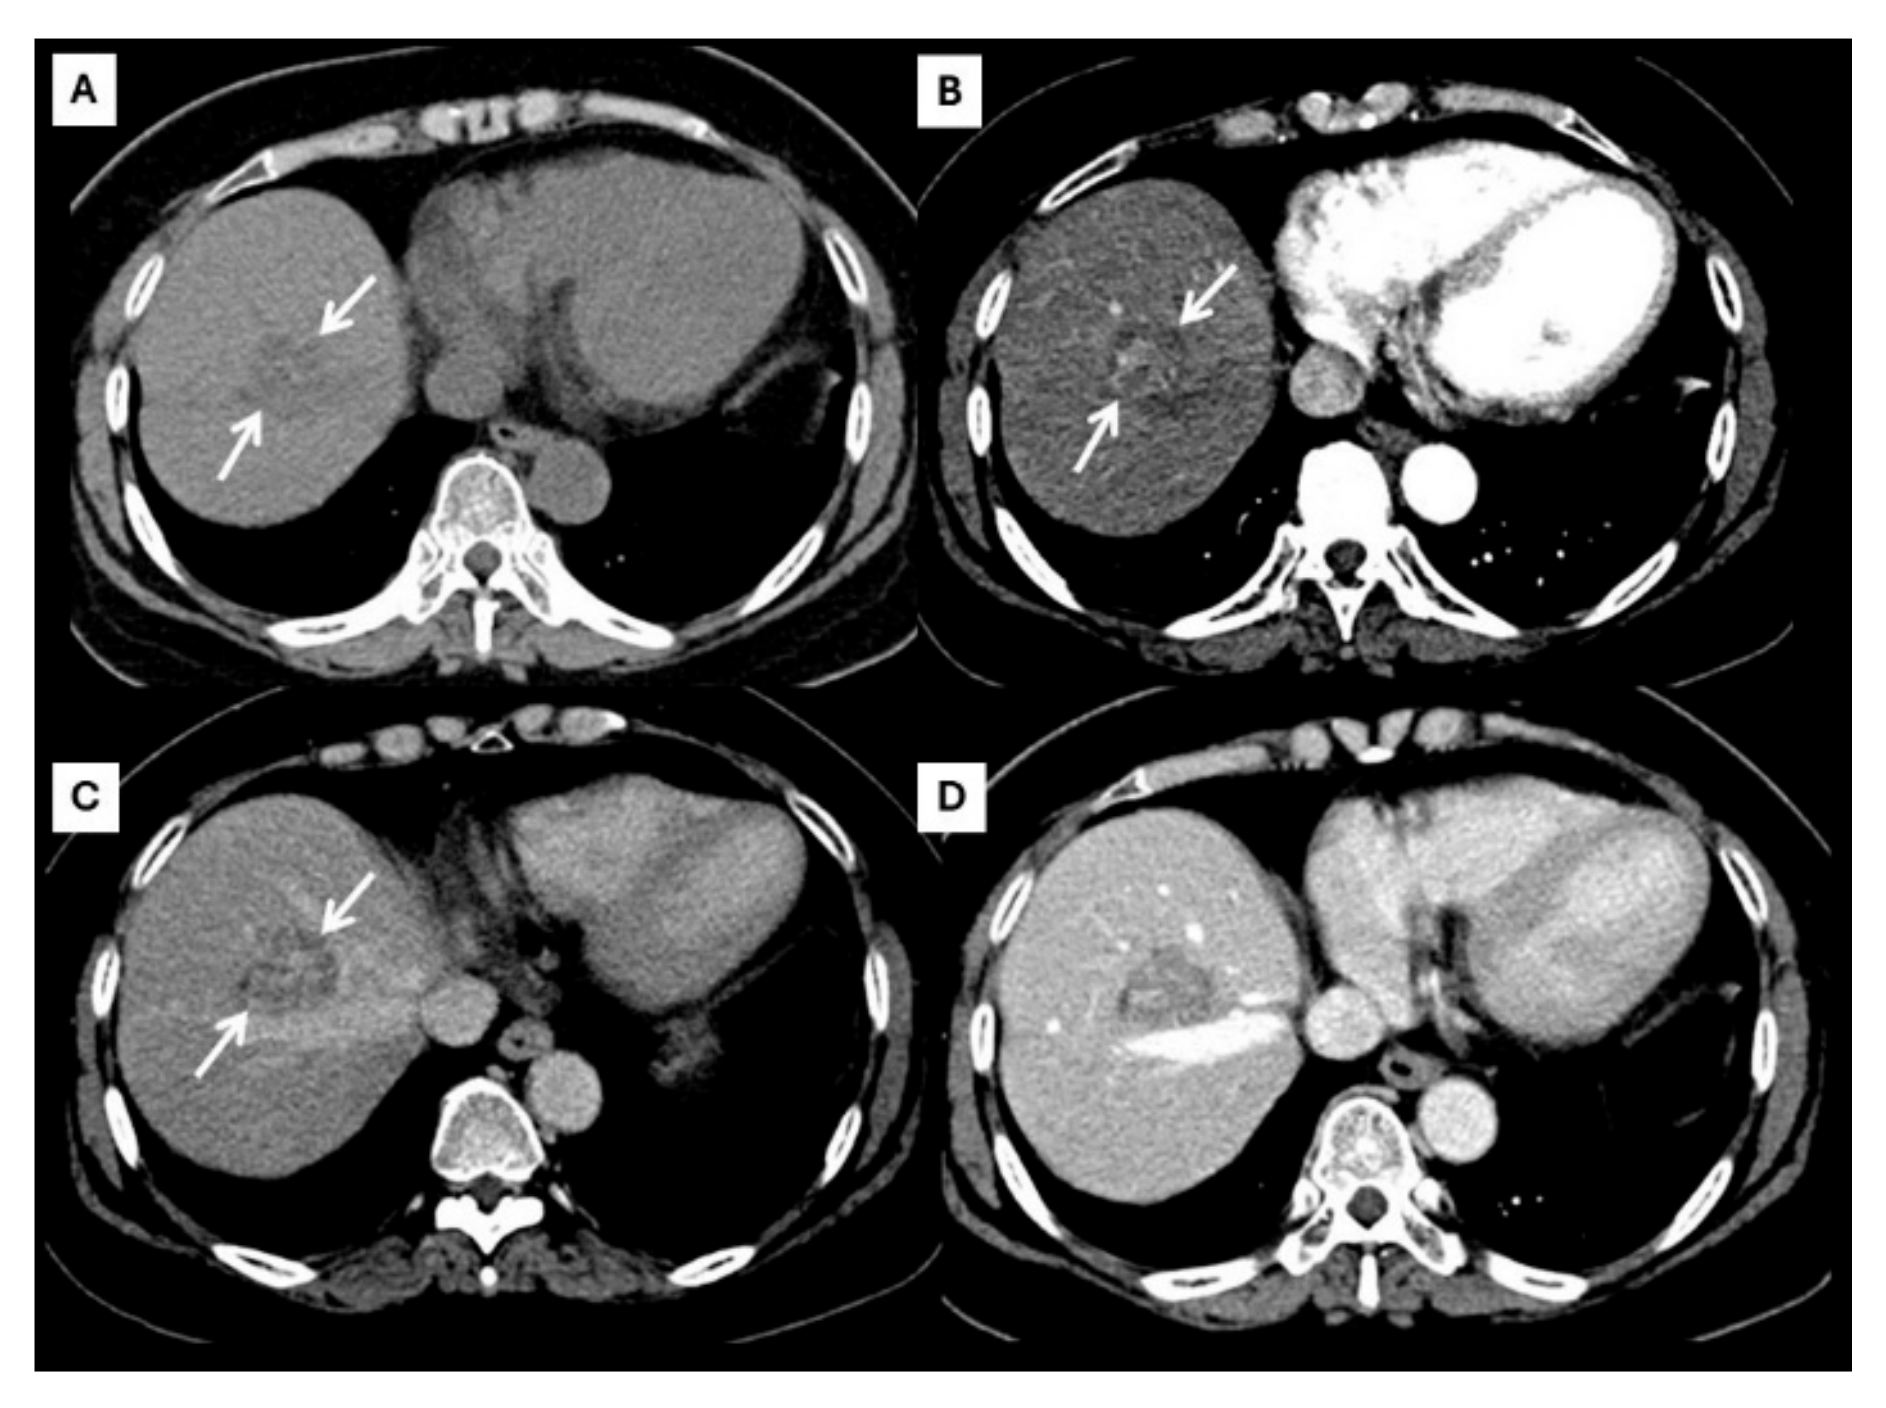

Figure 4.

CT findings of atypical ICC. Pre-contrast (A), arterial (B), portal venous (C), and delayed (D) post-contrast sequences demonstrate a mass with non-rim arterial hyperenhancement ((B), arrow) and progressive centripetal enhancement in the later phase ((C,D), arrow).